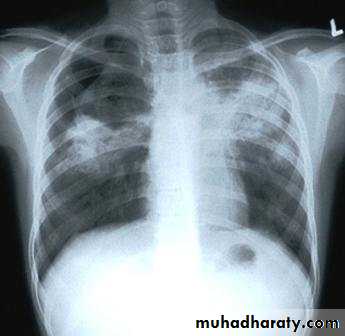

Chest x-rayTuberculin skin test (Mantoux skin test):